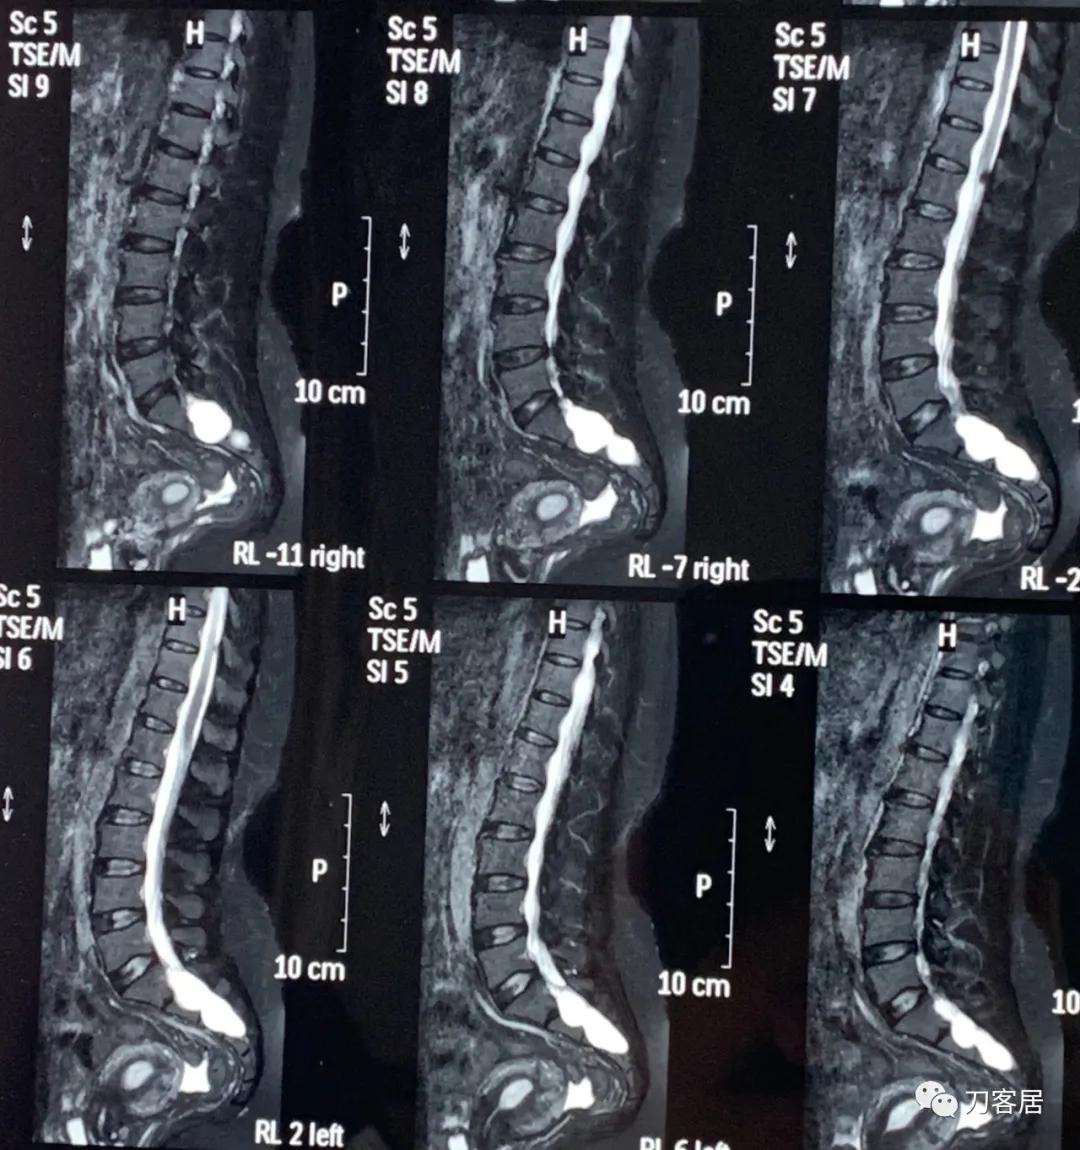

20160217患者骶管囊肿术前的腰骶椎磁共振